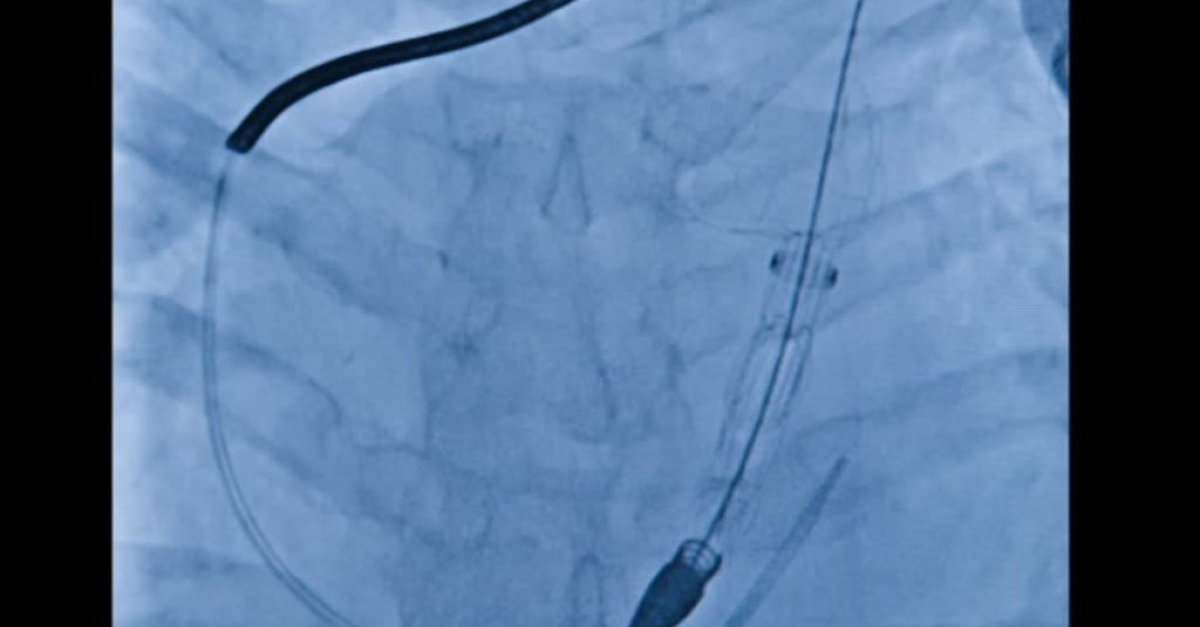

Roma, 21 lug. (askanews) - Hanno preso il via in Italia i primi impianti del sistema Harmony Transcatheter Pulmonary Valve (TPV), una tecnologia innovativa sviluppata da Medtronic, azienda leader di Healthcare Technology, che offre una soluzione alternativa alla chirurgia a cuore aperto per i pazienti con cardiopatie congenite.Il sistema Harmony rappresenta una svolta clinica per centinaia di pazienti che, fino ad oggi, erano destinati a interventi multipli a cuore aperto nel corso della vita e consente ai medici di trattarli in modo più sicuro ed efficace, migliorando la loro qualità della vita. Il dispositivo, già impiantato con successo in oltre 2.800 pazienti a livello internazionale, è ora disponibile anche in Italia in cinque centri ospedalieri di riferimento per la cardiologia pediatrica e congenita: Ospedale Pediatrico Bambino Gesù di Roma; Azienda Ospedale-Università di Padova; Policlinico Sant'Orsola-Malpighi di Bologna; IRCCS Policlinico San Donato e Ospedale Papa Giovanni XXIII di Bergamo.Le cardiopatie congenite colpiscono circa 40.000 neonati ogni anno in Europa e la popolazione adulta affetta è pari a oltre 2,3 milioni di persone . Circa il 20% dei pazienti presenta malformazioni del tratto di efflusso del ventricolo destro (RVOT), che compromettono il passaggio del sangue tra cuore e polmoni. Per molti pazienti con queste anomalie una sostituzione della valvola polmonare è necessaria nel tempo, ma tradizionalmente richiedeva un nuovo intervento a cuore aperto. Ora, con il sistema Harmony , è possibile eseguire l'impianto in modo mininvasivo, riducendo significativamente i rischi e i tempi di recupero.L'insufficienza della valvola polmonare è una condizione in cui questa valvola, situata tra il ventricolo destro del cuore e l'arteria che porta il sangue ai polmoni, non funziona come dovrebbe. Normalmente, il suo compito è quello di far passare il sangue verso i polmoni, dove si arricchisce di ossigeno, e poi chiudersi per impedire che torni indietro. Quando la valvola non si chiude bene, una parte del sangue torna nel cuore invece di proseguire il suo percorso. Questo costringe il ventricolo destro a lavorare di più per mantenere un flusso efficace, uno sforzo che con il tempo può diventare problematico. In una fase iniziale il cuore riesce ad adattarsi, ma col passare degli anni possono comparire sintomi come stanchezza, fiato corto anche con sforzi lievi, e nei casi più gravi aritmie, scompenso cardiaco e rischio di morte. Per evitare che la situazione peggiori, quando l'insufficienza è significativa si interviene con la sostituzione della valvola polmonare. Questo permette di ristabilire il normale flusso del sangue verso i polmoni e di ridurre il carico sul cuore, migliorando la qualità e le prospettive di vita del paziente.Harmony TPV è progettata per offrire una valida alternativa all'intervento chirurgico tradizionale di sostituzione della valvola polmonare. La procedura di impianto avviene infatti tramite un sistema transcatetere e consente un recupero più rapido e minori rischi operatori. La procedura di impianto valvolare transcatetere ha alcuni vantaggi fondamentali rispetto alla chirurgia - sottolinea il Prof. Massimo Chessa Responsabile del Centro di cardiologia ed emodinamica pediatrica e del congenito adulto dell'IRCCS Policlinico San Donato - permette un approccio meno invasivo e un recupero più veloce per il paziente spesso giovane e già sottoposto a vari interventi chirurgici. Inoltre, benché vi possano essere rischi aritmici legati alla procedura, va ricordato che anche l'approccio chirurgico, che per sua natura prevede la creazione di cicatrici, non può preservare il paziente da tali rischi. I dati clinici a tre anni confermano risultati eccellenti in termini di funzionalità valvolare, adattabilità anatomica, sicurezza e durata dell'efficacia. L'arrivo del dispositivo Harmony ha consentito di estendere la possibilità di trattamento per via transcatetere a un numero maggiore di pazienti - commenta il Prof. Biagio Castaldi dell'Azienda Ospedale - Università di Padova. Il device è risultato altamente versatile, in grado di adattarsi a diverse conformazioni anatomiche e di semplice utilizzo sia nella fase di montaggio che in quella di impianto. Gli anni e le risorse investiti da Medtronic nella progettazione della valvola ci fanno pensare che gli studi a lungo termine confermeranno i risultati finora ottenuti in termini di sicurezza ed efficacia .Questa innovazione consente di ridurre significativamente il carico clinico e psicologico associato agli interventi ripetuti, migliorando la qualità della vita dei pazienti e riducendo le interruzioni nelle attività quotidiane, soprattutto nei soggetti più giovani.A conferma del valore aggiunto che questa innovazione rappresenta nella pratica clinica quotidiana, il Dott. Duarte Saraiva Martins, cardiologo interventista dell'Unità complessa di Cardiologia 2 - Cardiopatie congenite del bambino e dell'adulto dell'ASST Papa Giovanni XXIII, evidenzia come: oltre alla grande versatilità di questa nuova valvola, un elemento innovativo e clinicamente molto utile è la piattaforma digitale messa a disposizione da Medtronic, che aiuta i medici a capire se un paziente può ricevere l'impianto della valvola Harmony. Grazie a immagini dettagliate del cuore, questa tecnologia permette di programmare l'intervento in modo più semplice e sicuro. Questo rende la procedura più rapida e riduce anche l'esposizione dei pazienti ai raggi X .